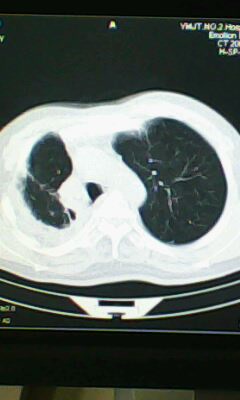

标题: CT25675:男 71 肺癌部分切除术后 3年 [打印本页]

标题: CT25675:男 71 肺癌部分切除术后 3年

两肺感染性病变,右侧肺膨胀不全,左侧上叶结节影及左侧颈部淋巴结肿大建议复查。

右肺炎症,左肺炎症。

右侧胸膜肥厚。

两肺感染性病变\\右侧胸膜增厚

术后改变,双肺内纤维索条影考虑与放疗有关。